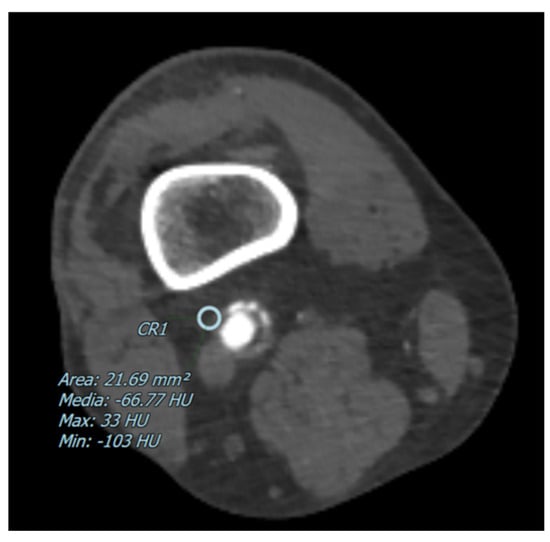

The degree of arterial stenosis was categorized into four distinct classes: <25%, 25–50%, 50–70%, and >70%. Perivascular adipose tissue (PVAT) density, measured in Hounsfield Units (HU), was determined by positioning a 5 mm circular region of interest (ROI) adjacent to the vascular wall, as shown in Figure 1 and Figure 2. Additionally, for each of these vascular segments, both the degree of stenosis and the corresponding PVAT attenuation values were quantitatively assessed.

Figure 1.

The figure shows an example of a CT image with a pointed perivascular adipose tissue density in a patient with a partial arterial stenosis of the popliteal artery. The blue circle represents the ROI where the perivascular adipose tissue density has been measured in Hounsfield Units (HU).